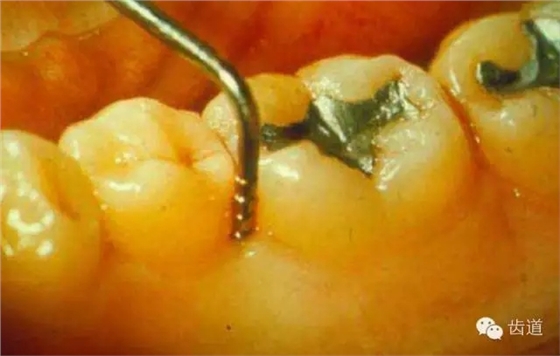

(3)其他刺激物:不良修復(fù)體、食物嵌塞等。